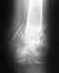

Диагноз представлен в несколько поверхностной форме. Переломы вертлужной впадины подразделяются на множество разновидностей, и показания к операции определяются далеко не только наличием свободных вргментов в суставе, что само по себе является показанием к операции. Однако задачи операции не ограничиваются лишь удалением свободных фрагментов, необходимо воссоздание конгруэнтной суставной поверхности.